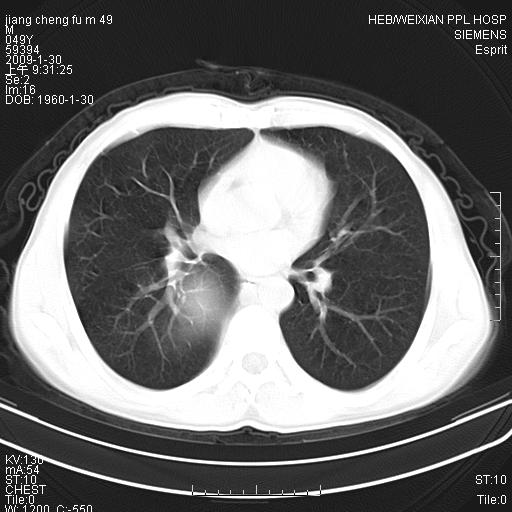

男性,49岁,主因胸痛,右肺呼吸音低。胸片提示肺占位

考虑右侧脊柱旁沟囊性病变。1:支气管囊肿或食管囊;2:神经源性肿瘤。

右后纵隔囊性占位;考虑为:1)淋巴管囊肿。2)食管囊肿。建议:进一步检查。

右后纵隔囊性占位,建议先做增强,后做穿刺活检。

在分析这个病变时,首先病灶边界清晰,但其内密度不均匀,有条索状状实性成分,肿块的外侧壁亦呈一不均匀的厚壁改变,因此支气管囊肿的可能性不大。主要考虑神经源性肿瘤(主要考虑神经鞘瘤,因为它囊变的机率比较高),其次考虑肺膈离征,行增强扫描如发现来自胸主动脉供血动脉血管可确诊。

考虑右侧脊柱旁沟囊性病变,囊骨有分隔,囊壁较厚。1:神经源性肿瘤;2:食管囊肿或淋巴管囊肿。支持!

囊状肿块内有线样软组织分隔,支气管囊肿及食管囊肿可不考虑。我考虑:1、囊性肺膈离征(需要增强扫描来排除)。2、神经鞘瘤。3、淋巴管囊肿。